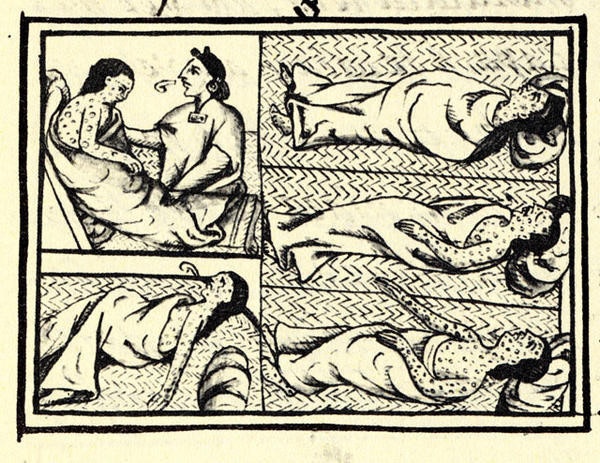

▲誰要去照顧得了天花的病人?( Photo Credits: Wikimedia Commons)

金納在18世紀末發明人類史上第一個疫苗,但人類認知到免疫作用存在的時間遠遠早過18世紀。根據先前的研究顯示,西元前430年的雅典時代,希臘人就瞭解已經生過一次天花並存活下來的人,不會再得第二次天花,因此他們常被叫去照顧其他受到天花感染的病人。